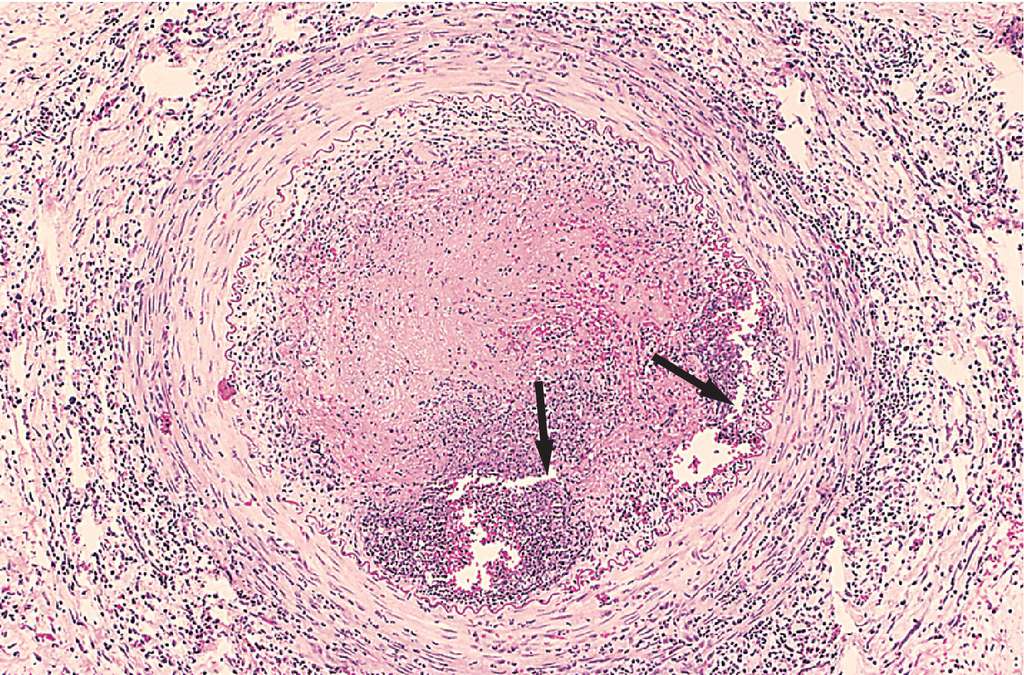

Correct all you're your grammar errors instantly. Try it now. Thromboangiitis obliterans (Kumar et al, 2007)